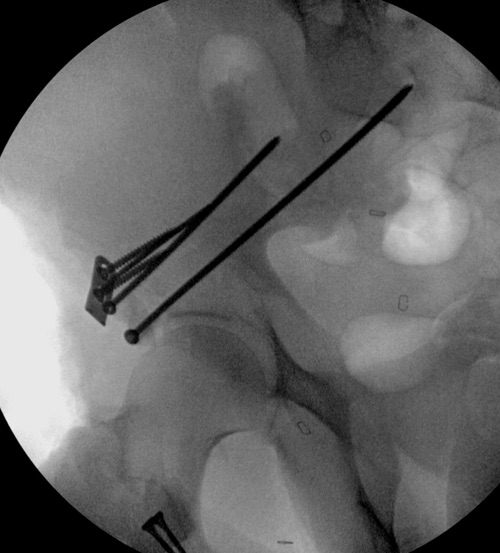

Появились новые проекции. Да, это высокий перелом передней колонны левой вертлужной впадины со смещением.

Представленные слайды Александром из Севастополя, имеет ценность, но, кроме inlet, остальные стандартные Judet рентген снимки должны показать правоту принятого решения. Возможно, здесь фиксация перелома вертлужной впадины, но по рентгену трудно понять!

Здесь пример перелома передней стенки, где сохранен принцип фиксации передней колонны. Для доступа Smith Petersen с остеотомией ASIS. Мышца сарториус отодвинута, и сделана ре-фиксация на свое место винтами. При хорошем обзоре, наличие Farabeuf или Jungblud forceps облегчит репозицию.